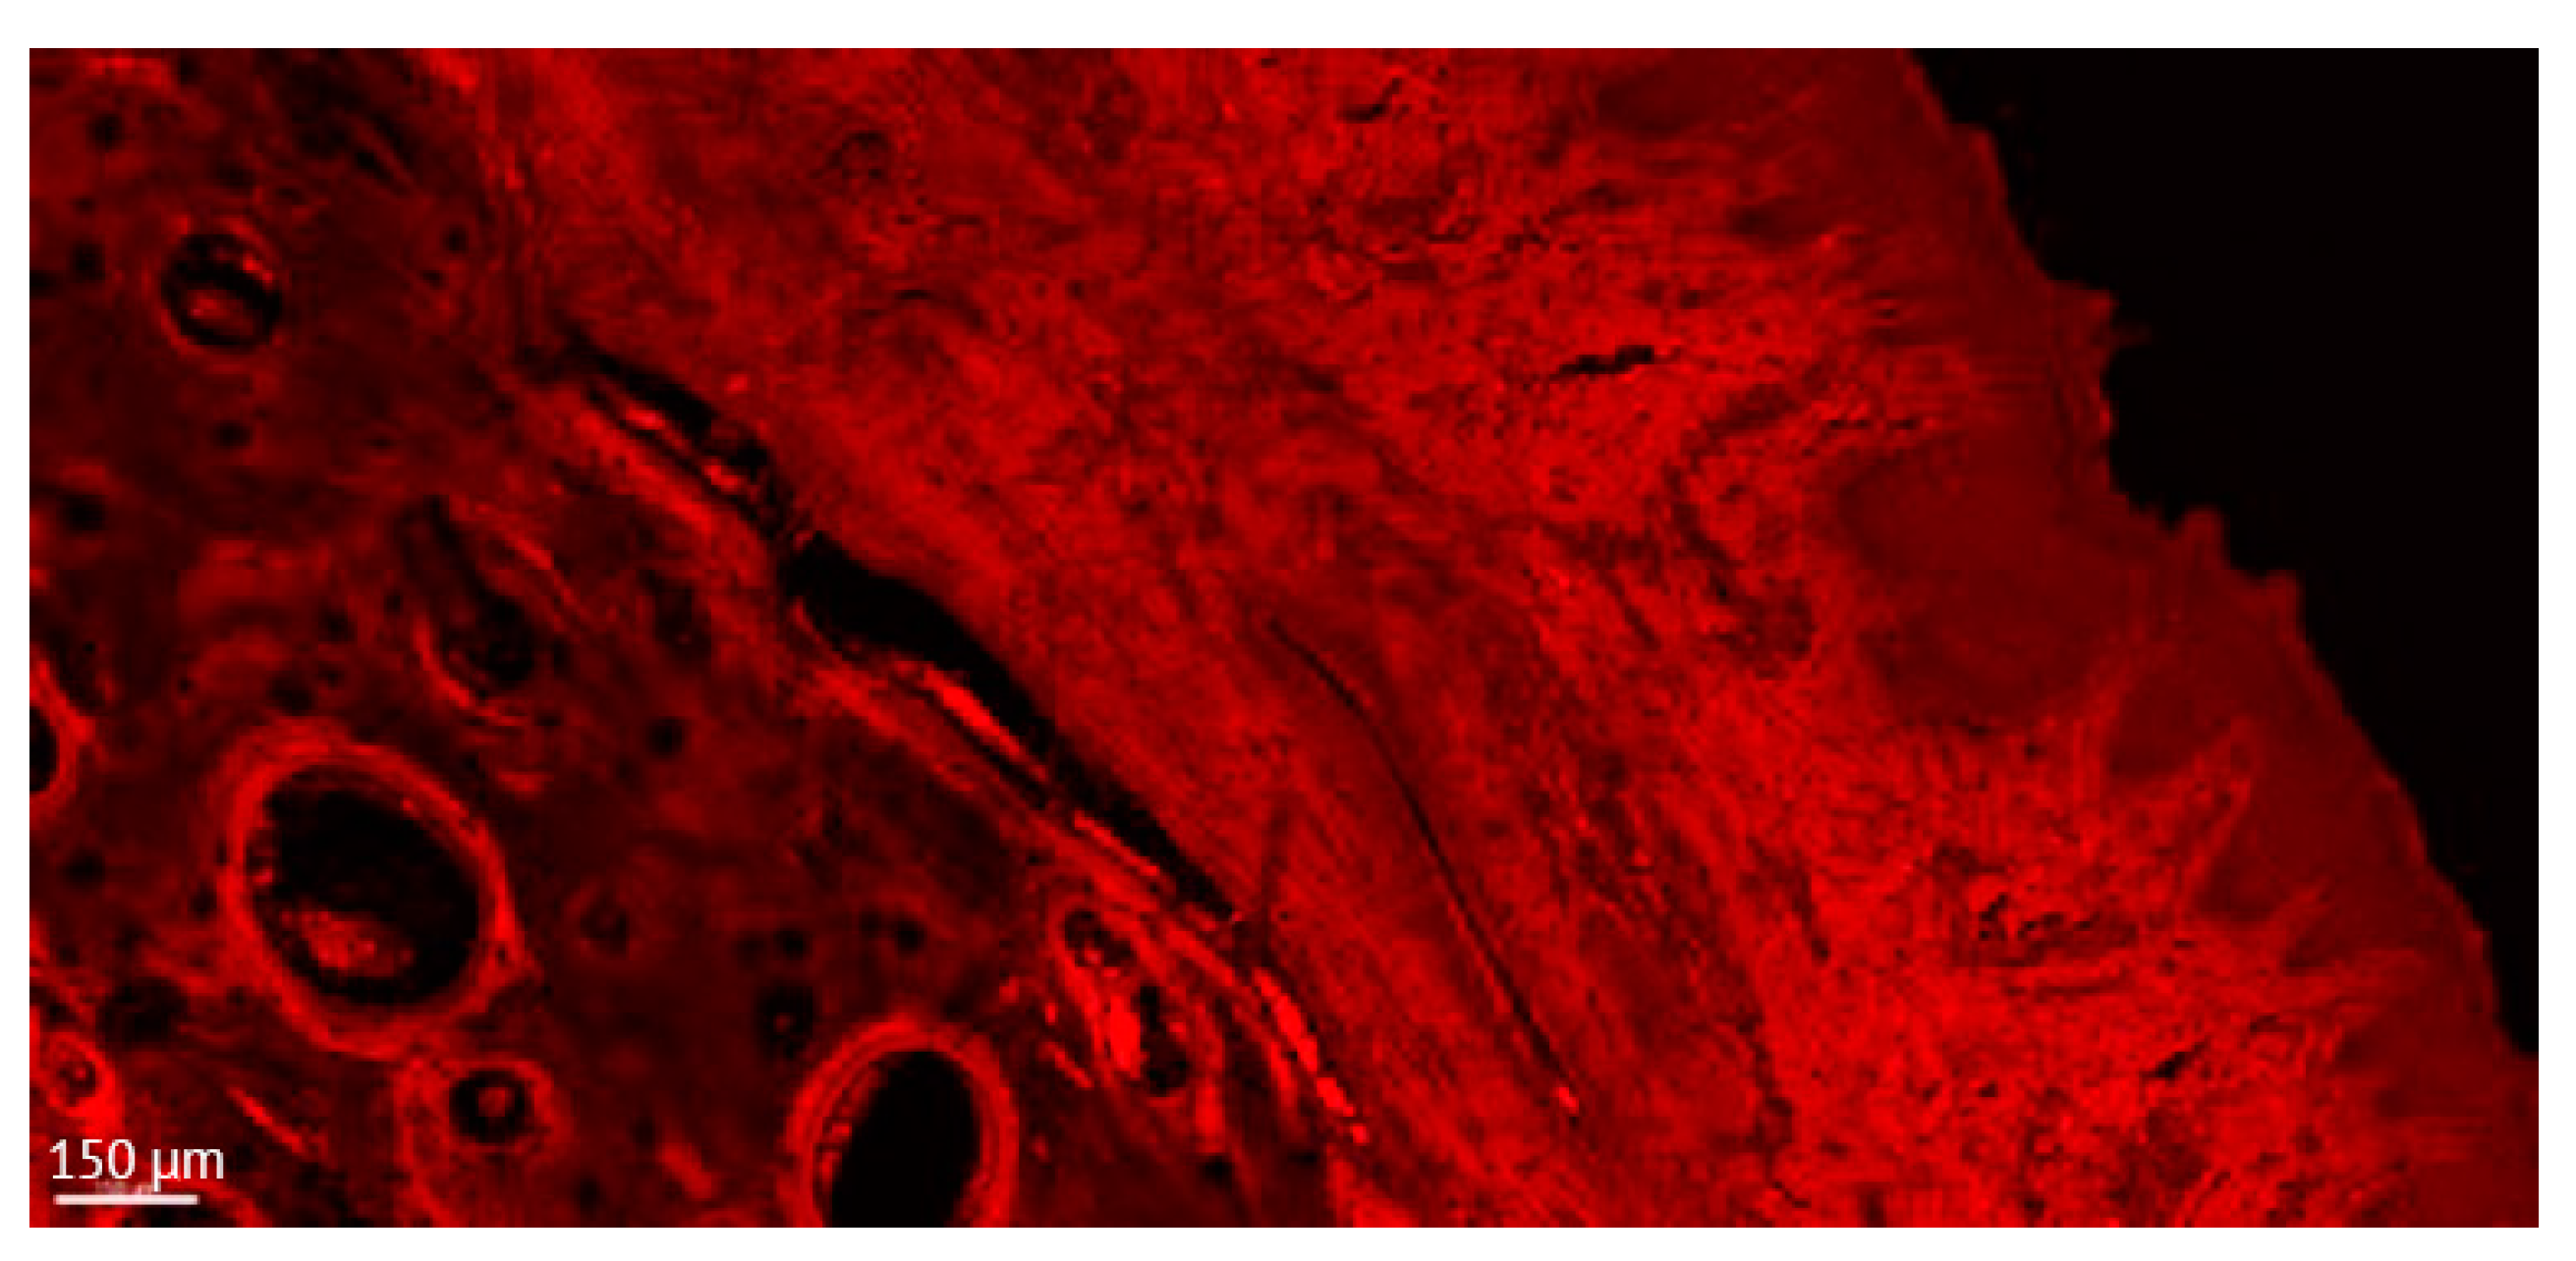

Figure 5.

Detailed aspect of the soft tissue and bone in a thick section of a non-ligated implant. Note the presence of acanthosis of the covering epithelium. ICT is present in contact with bone and implant, promoting an active bone resorption. (implant #2, oral aspect; bar, 150 µm).

Early authors noted that a thickness of 80 to 100 µm (taking into account about 20 µm for the layer of glue or cement) should be sufficient for all the methods of microscopic examination of non-demineralized specimens and preparing thinner sections down to a thickness of 5 to 10 µm is, in most cases, unnecessary, requiring machine grinding and being associated with more risk of failure. However, they mentioned that thin sections (0.5 to 5 µm thickness) can provide additional information about cellular details of the implant-tissue interface [60]. In our study, such information was provided under CSLM by the “thick” sections (Figure 4).